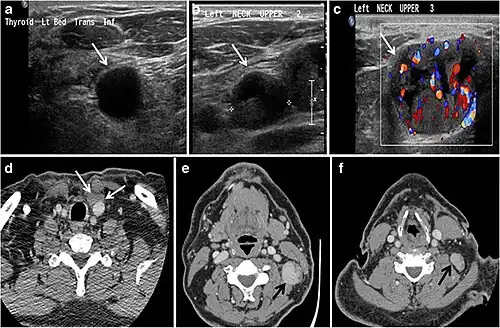

Fig. 7. A 51-year-old female patient post total thyroidectomy for PTC with elevated thyroglobulin measurement. an Axial non-enhanced CT scan of the neck at the level of the thyroid bed demonstrates a well-defined, rounded, homogenously dense soft tissue situated between the trachea and left internal jugular vein (white arrow). b Transverse ultrasound image of the neck demonstrates a well-defined, homogeneous, hypoechoic soft tissue nodule measuring 6 mm (white arrow) with no detected micro-calcifications. Biopsy showed a predominantly residual normal thyroid tissue with micro-foci of PTC.[1] -

Fig. 8. A 48-year-old male patient post total thyroidectomy with PTC recurrence. a Transverse greyscale ultrasound of the neck demonstrates a left thyroid bed heterogeneous, predominantly hypoechoic irregular lesion with calcifications (white arrow). b A spot image of iodine 123 total body scan of the neck demonstrate a focus of abnormal radiotracer uptake at the left thyroid bed (Black arrows) between the annotated markers. c Enhanced axial CT scan of the neck demonstrates an enhancing large left thyroid bed mass (white arrow) with no calcifications. The lesion exerts a mass effect on the oesophagus (black arrow) and is inseparable from the trachea.[1] -

Fig. 9. A 58-year-old male patient with persistence PTC at thyroid bed with hypervascular nodal metastasis. a–c Transverse greyscale and colour Doppler neck ultrasound demonstrate hypoehoic soft tissue in the left thyroid bed (white arrow in a). There are a heterogeneous enlarged lymph nodes at level 2 and 3 with markedly increased vascularity (white arrow in b and c). d–f Enhanced axial CT images of the neck demonstrate a 2.7 × 1.4 cm hypodense soft tissue lesion anterior to the left carotid sheath (white arrow). There are left-sided enhancing abnormal and enlarged lymph nodes at cervical level 2 and 3 (black arrows).[1]